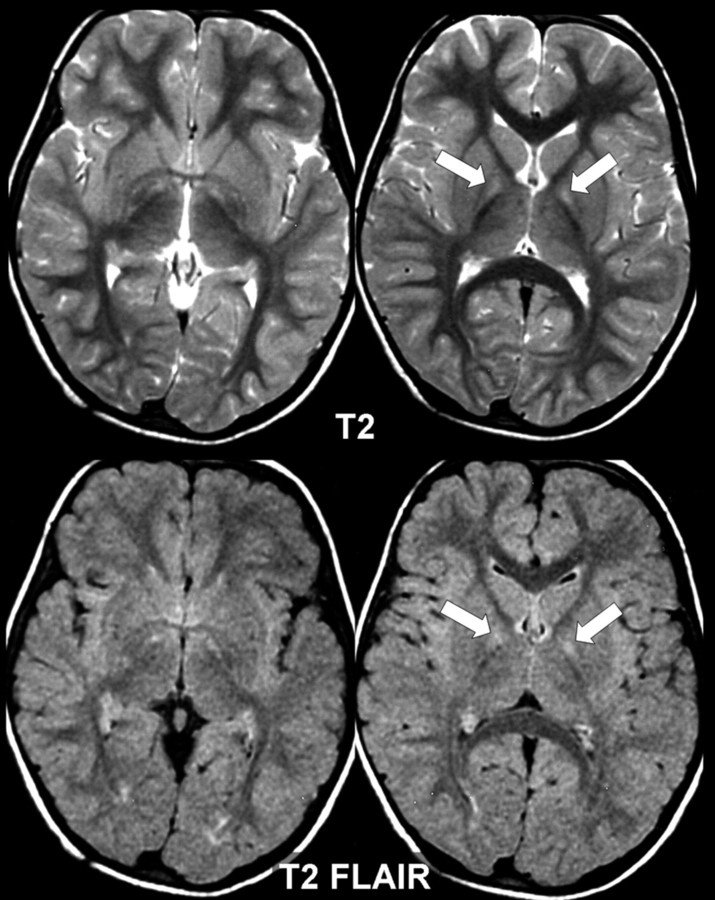

MRI

Magnetic Resonance Imaging

magnetic field and pulses of radio wave energy to make pictures of organs and structures inside the body

images produced by MRI are then processed using segmentation techniques